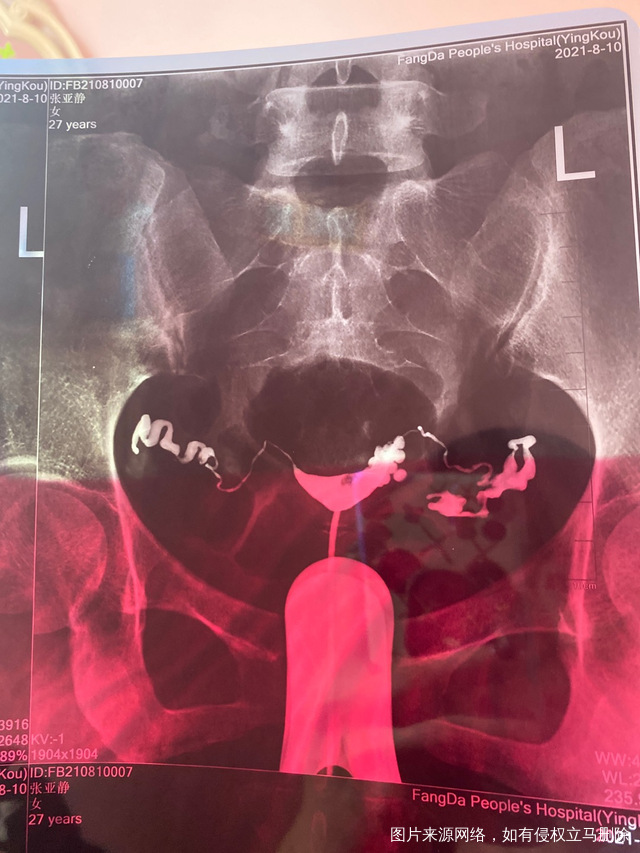

做完输卵管造影第六天了小腹还是感觉沉甸甸的如

可以热敷腹部,如果有发热,腹痛加剧,白带量多,有异味,随时就医